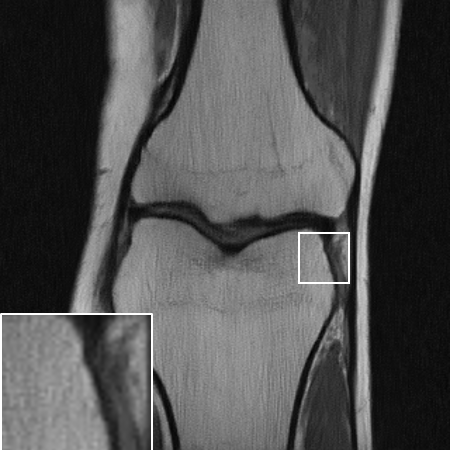

Table LABEL:tab:quant_results summarizes the results for the various experimental settings, comparing the performance of the above-mentioned benchmarks to ours. When compared to TV [6], our method achives an improvement of dB-dB in the peak-signal-to-noise ratio (PSNR). Similar results are observed for the structural-similarity measure (SSIM, about points improvement). As expected, the supervised model outperforms the proposed SSL method. However, it seems that at least for the lower distortion rates, this gap is surprisingly small. A visual inspection of the results over one slice is provided in Fig. 3. As can be observed in the zoomed-in region, our method manages to restore finer details better than the TV-based method, and even approaches the restoration levels of the supervised model in the lower distortion rates. As evident both quantitatively and visually, the TV-based method completely fails on the dealiasing task, whereas our SSL method seems to significantly alleviate the reconstruction artifacts.